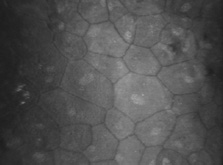

The human corneal endothelium is a single layer of 400,000 to 500,000 cells. Confocal microscopy provides views of this cell layer that surpass the details seen under specular microscopy (Figs. 19 and 20). Cells are 4 to 6 μm in height and 20 μm in width, and their posterior surfaces are predominantly hexagonal when viewed under specular microscopy (Fig. 21). Cross-sectional views with electron microscopy show that cell lateral walls are extremely tortuous and interdigitate with extensive folds and finger-like projections. It has been estimated that the total paracellular path length may be 10 times longer than the total height of the cell.90 Numerous gap junctions along the lateral membranes provide cell-to-cell cytoplasmic communication as evidenced by the presence of connexin 43 and the spreading of fluorescent dye from an injected cell to surrounding cells (Fig. 22).91

Fig. 19. Confocal microscopic transverse image of the human corneal endothelium in vivo. In the young normal cornea, the majority of the cells will have a hexagonal outline and they will be fairly uniform in size. The dark spots near the center in many of the cells may represent the central endothelial cilium (500×). (Courtesy of Nidek Technologies.)